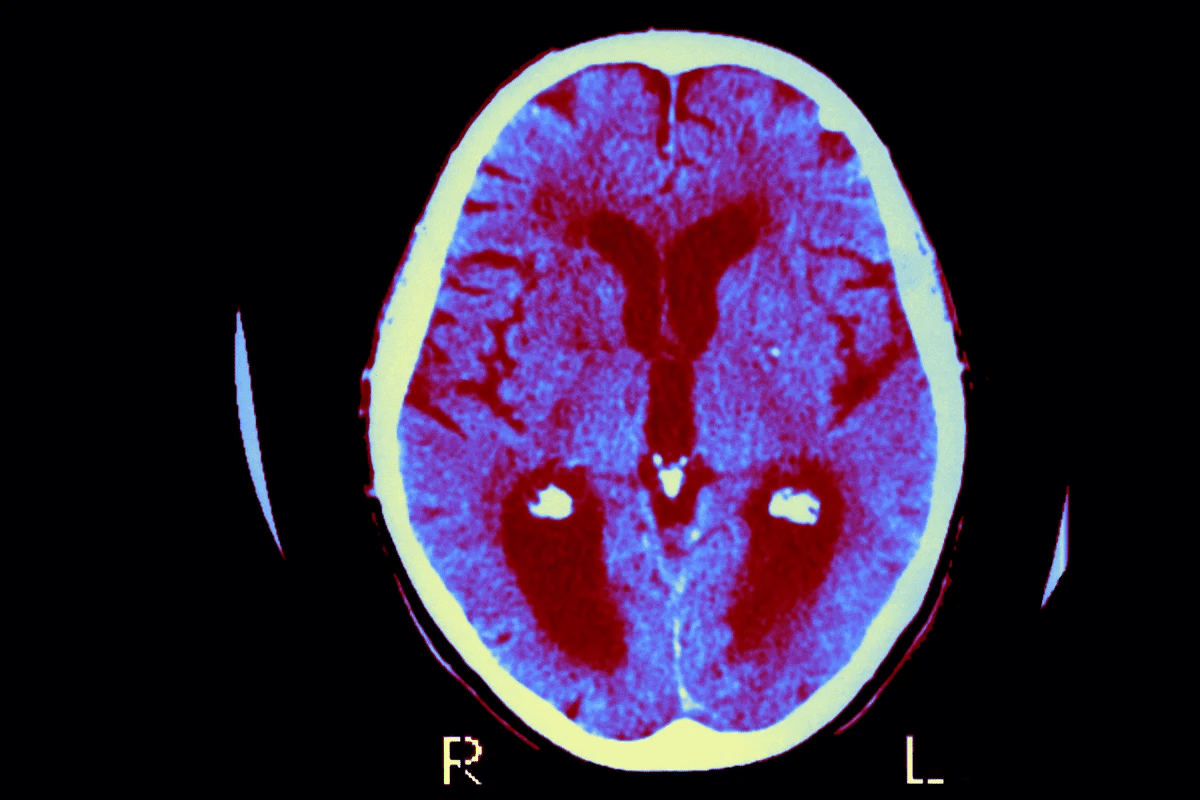

Neuroimaging Techniques

Neuroimaging is vital for spotting CAA. MRI (Magnetic Resonance Imaging) and CT (Computed Tomography) scans help find signs of CAA. These include lobar intracerebral hemorrhages and microbleeds.

Gradient Echo MRI sequences are great for finding microbleeds. These are a big sign of CAA. These tools help doctors diagnose and track how the disease is progressing.